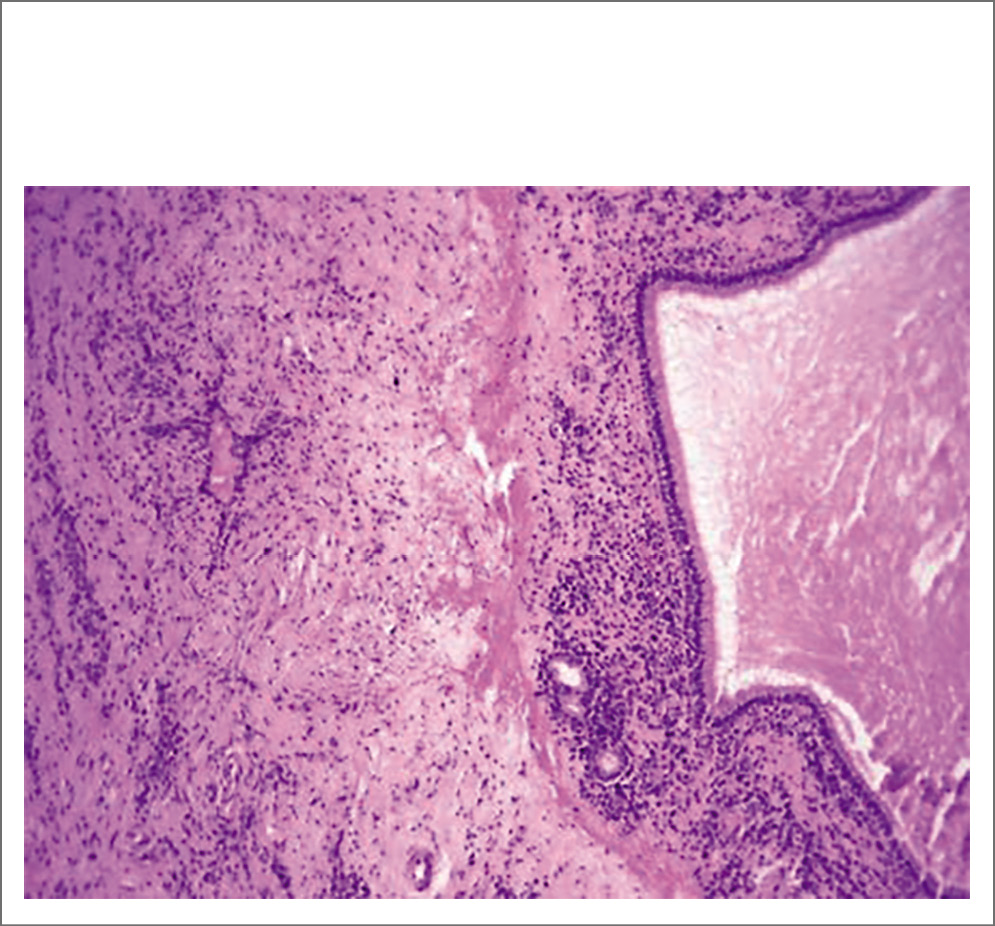

После эндоскопической визуализации полости носа и регистрации слева полипозных вегетаций с характерной окраской и консистенцией, обильным выделением густого слизистого секрета (рис. 2) и предыдущей КТ носа и ОНП пациентке выполнена МСКТ с контрастным усилением, заключение: тотальное затемнение левой гайморовой пазухи, клеток решетчатого лабиринта с разрушением медиальной стенки ВП и проникновением в полости носа, смещение носовой перегородки и компрессия средней носовой раковины, наличие группы гиперденсивных включений округлой формы, контраст не накапливается (рис. 3). После выставления диагноза левостороннего хронического ПРС, мицетомы гайморовой пазухи и проведения соответствующей предоперационной подготовки пациентке выполнена гайморотомия по Колдуэлл–Люку, этмоидотомия слева. Отмечено в левой ВП наличие органических субстратов высокой плотности. Интраоперационно взятые подозрительные фрагменты поврежденных тканей направлены на гистологическое исследование с соответствующим диагнозом (рис. 4).

Рис. 2. Назальные полипы в носовом ходе слева, густой слизисто-гнойный секрет.

Через 10 дней получен ответ с описанием признаков хронического воспаления и полипоза носа: отечная, фиброзная или слабомиксоидная строма, инфильтрирована смешанными воспалительными клетками, включая лимфоциты, плазматические клетки, эозинофилы, нейтрофилы и тучные клетки, поверхностный эпителий проявляется изъязвлением или плоскоклеточной метаплазией, подслизистые железы уменьшены или отсутствуют. Заключение гистологического исследования: множественные аденоматозные фиброзно-отечные полипы носа. Данные за мицелий отсутствуют (рис. 5–7). После обращения с просьбой повторно исследовать гистологические блоки на наличие грибов морфологами были использованы элективные методы обработки (постановка ШИК-реакции, метод Гомори) и обнаружены элементы мицелия грибов (рис. 8). Импрегнация по Гомори–Грокотт метинамином серебра не проводилась.

Рис. 5. Воспалительный синоназальный полип. Общий вид. Окраска гематоксилином и эозином. ×50.

Рис. 6. Структура полипа. Воспалительная инфильтрация, уменьшение количества слизистых желез, отечная миксоидно- фиброзная строма. Окраска гематоксилином и эозином. ×200.